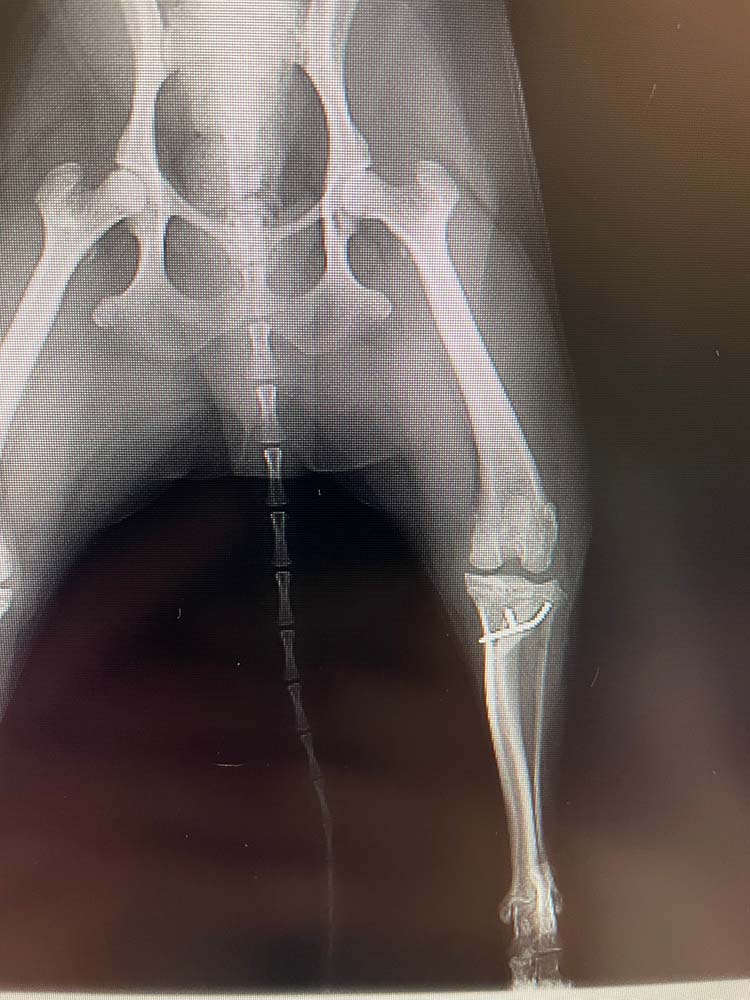

- 脛骨粗面転移

膝蓋靱帯の脛骨への付着部を骨切りし、滑車溝の真下に移動させる手技

また、脛骨粗面転移に関しては、Polaris Vetでは全ての症例での実施とはせず、脛骨の捻れの程度や膝関節における軟部組織での回旋の程度によって適応可否の判断をしています。

脛骨粗面転移は脛骨の膝蓋靱帯付着部で骨切りを行い、ずらした場所にピンで固定するという方法になります。

そのため、骨癒合が得られるまでの安静期間が長くなることや合併症発生リスクが高くなるデメリットも存在します。

脛骨近位の捻転が軽度であれば、粗面転移を実施せずとも良好に整復できる症例も多く、

基本手技に組み入れてはいないと言っても、実際の手術の際は、手術中の膝の可動状況や脛骨の状態を見て、粗面転移が追加になっても対応ができるように準備を整えてから実施しています。